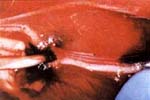

En el lado derecho, el injerto vascularizado se preparó con la siguiente técnica: después de identificar el pedículo vascular en el lado proximal del nervio (Figura 1); éste fue seccionado proximal y distalmente al pedículo sin retirarlo de su sitio en una longitud de 30 mm.

La permeabilidad del pedículo y la viabilidad del injerto se establecieron comprobando el sangrado en los extremos del nervio seccionado. Una vez identificados los fascículos, se extrajo el contenido intraneural del perineurio mediante una tracción suave ejercida en el lado proximal, retirando parcialmente los fascículos del primer grupo fascicular (Figura 2).